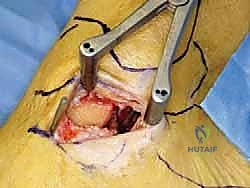

الخطوة الثالثة: الشق الجراحي والوصول الآمن

يتم عمل شق جراحي دقيق ومدروس على الجانب الداخلي للكاحل، خلف وتحت الكعب الإنسي. يستخدم الدكتور هطيف تقنيات تشريحية دقيقة لحماية الهياكل الحيوية المحيطة، وخاصة العصب الصافن (Saphenous Nerve) والوريد المرافق له، لتجنب أي تنميل أو ألم عصبي مزمن بعد الجراحة.

الخطوة الرابعة: تقييم وإصلاح رباط الدالية (Repair vs. Reconstruction)

بمجرد الوصول إلى رباط الدالية، يتم تقييم درجة التلف:

* الإصلاح المباشر (Direct Repair): إذا كانت أنسجة الرباط الممزقة ذات جودة جيدة (عادة في الإصابات الحديثة)، يقوم الدكتور هطيف بخياطتها مباشرة. يستخدم خطاطيف تثبيت عظمية (Suture Anchors) صغيرة جداً ومصنوعة من مواد متوافقة حيوياً (تذوب مع الوقت أو من التيتانيوم) لغرس الخيوط القوية في عظمة الكعب الإنسي، ثم يتم سحب الرباط الممزق وتثبيته بقوة في مكانه التشريحي الأصلي.

- إعادة البناء (Reconstruction): في الحالات المزمنة حيث يكون الرباط الأصلي قد تليف، تآكل، أو أصبح غير كافٍ للاستخدام، يلجأ الدكتور هطيف إلى تقنية "إعادة البناء". تتضمن هذه التقنية المتقدمة استخدام رقعة وترية (Graft)، إما من جسم المريض نفسه (Autograft - مثل أوتار الركبة أو وتر من القدم) أو رقعة صناعية متطورة. يتم حفر أنفاق ع